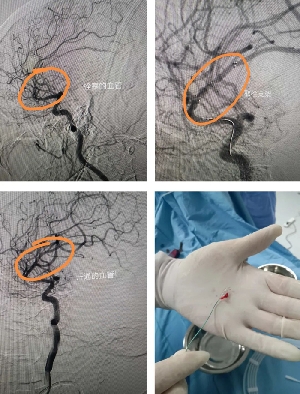

患者突發(fā)卒中,神經(jīng)介入緊急取栓救命!

患者老年女性,既往有先心病史,因心衰收住院。6月29日突發(fā)左側(cè)肢體偏癱,腦CT未見出血,診斷急性腦梗死。值班醫(yī)生立即聯(lián)系神經(jīng)內(nèi)三科副主任馬磊!馬主任認(rèn)為患者為心源性栓塞,立刻啟動應(yīng)急預(yù)案,建議緊急取栓!家屬簽字同意后,立刻將患者轉(zhuǎn)運(yùn)到介入室。造影提示患者為右側(cè)大腦中上干閉塞,大腦中動脈m2段閉塞,取栓困難,